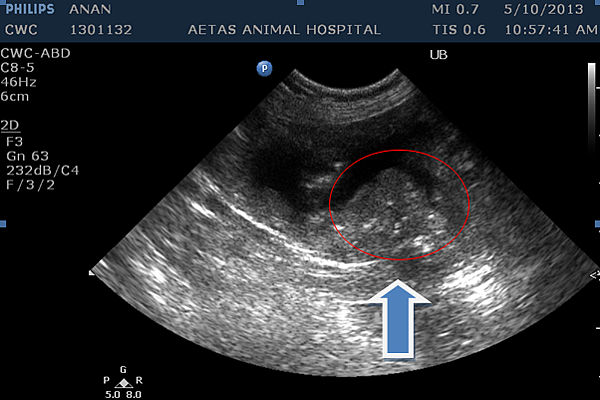

超音波是診斷膀胱腫瘤的第一個工具,除了檢查膀胱是否有腫塊出現之外,還可以評估是否有局部轉移的發生,不過嚴重的膀胱炎與膀胱腫瘤在超音波下難以辨認,所以還是必須依賴組織學切片。

超音波檢查: 箭頭處指出膀胱三角區處出現明顯腫塊